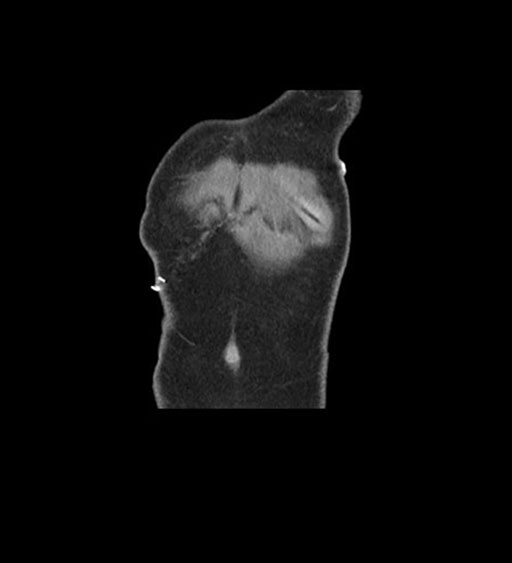

Coronal Arterial

Coronal Venous